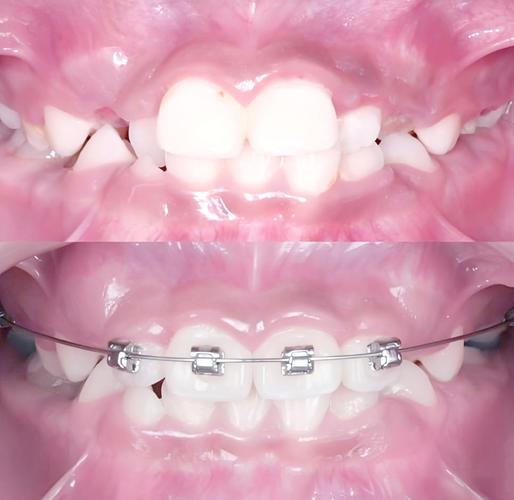

正畸治疗分为初期、调整期、保持期,不同阶段黏膜刺激的特点不同:

- 初期适应期(戴矫治器后1-2周):黏膜首次接触大量矫正装置,尚未建立适应性保护机制,易在托槽、弓丝对应部位出现局限性充血、糜烂,甚至形成“创伤性溃疡”,疼痛明显,影响进食。

- 调整期(每次复诊后1-3天):医生会根据牙齿移动情况调整弓丝(如更换更粗的弓丝、弯制“停止曲”)、更换结扎丝或添加牵引装置,此时牙齿位置尚未稳定,弓丝末端可能刺激新部位,或原有刺激点因装置调整再次受压。